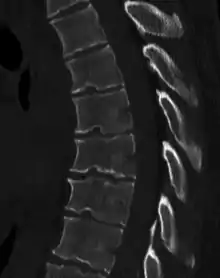

Scheuermann's disease is a self-limiting skeletal disorder of childhood. Scheuermann's disease describes a condition where the vertebrae grow unevenly with respect to the sagittal plane; that is, the posterior angle is often greater than the anterior. This uneven growth results in the signature "wedging" shape of the vertebrae, causing kyphosis. It is named after Danish surgeon Holger Scheuermann.[3][4][5]

In addition to the pain associated with Scheuermann's disease, many sufferers of the disorder have loss of vertebral height, and depending on where the apex of the curve is, may have a visual 'hunchback' or 'roundback'. It has been reported that curves in the lower thoracic region cause more pain, whereas curves in the upper region present a more visual deformity. Nevertheless, it is typically pain or cosmetic reasons that prompt sufferers to seek help for their condition. In studies, kyphosis is better characterized for the thoracic spine than for the lumbar spine.[6][7]